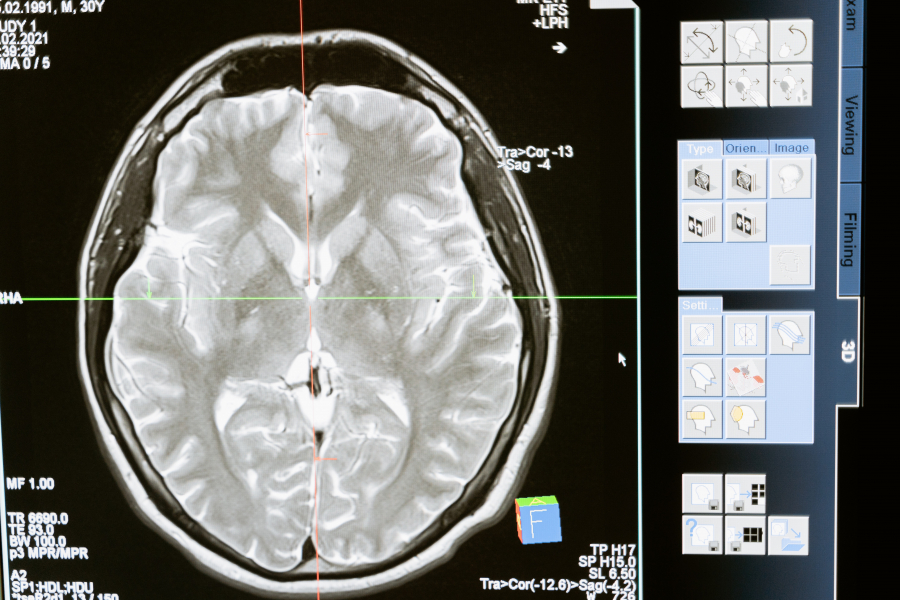

Διαπιστώθηκε ότι μεταξύ όσων είχαν πάθει εγκεφαλικό, σχεδόν οι μισοί (48%) είχαν πάρει κάποιο αντιεμετικό φάρμακο (domperidone, metopimazine ή metoclopramide) τουλάχιστον μία φορά μέσα στις τελευταίες 14 μέρες πριν το εγκεφαλικό. Οι άνδρες βρέθηκαν να έχουν τον μεγαλύτερο κίνδυνο (κατά 3,6 φορές) για εγκεφαλικό μετά από λήψη αντιεμετικού φαρμάκου.

Και τα τρία ανωτέρω φάρμακα βρέθηκαν να αυξάνουν τον κίνδυνο εγκεφαλικού, ιδίως μετά τις αρχικές δόσεις (συγκριτικά λιγότερο, κατά 2,5 φορές η domperidone, ενώ τα άλλα δύο κατά 3,5 έως 3,6 φορές). Η δράση τους στην κυκλοφορία του αίματος στον εγκέφαλο πιθανώς εξηγεί αυτή τη συσχέτιση.